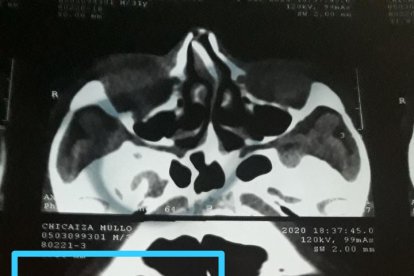

"Ese día me atacó con un fierro, me dio en la cabeza, estuve a punto de morir, porque por un milímetro el fierro atraviesa el cerebro; sin embargo perdí mi ojo derecho y la visión", lamenta la mujer.